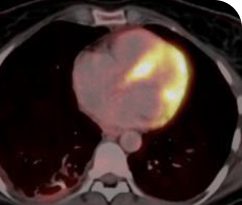

BASELINE

AFTER 31 MONTHS

33-YEAR-OLD MALE4

- 33-year-old male

- PRa after 2 cycles of VITRAKVI® (larotrectinib)

- Confirmed partial response on VITRAKVI lasting 55 cycles

Clinical presentation1

- Initially diagnosed at age 27

- Bulky disease in neck and thoracic involvement; metastatic, RAI-refractory papillary thyroid cancer

Response to VITRAKVI1,2

- Confirmed partial response (92.6% reduction in target lesions)

- Treatment continued for 55 cycles

- VITRAKVI was well tolerated; patient did not have to discontinue due to AEa

- No treatment interruptions or dose reductions

Response in primary and metastatic lesions1

Images courtesy of Dr Steven Waguespack.